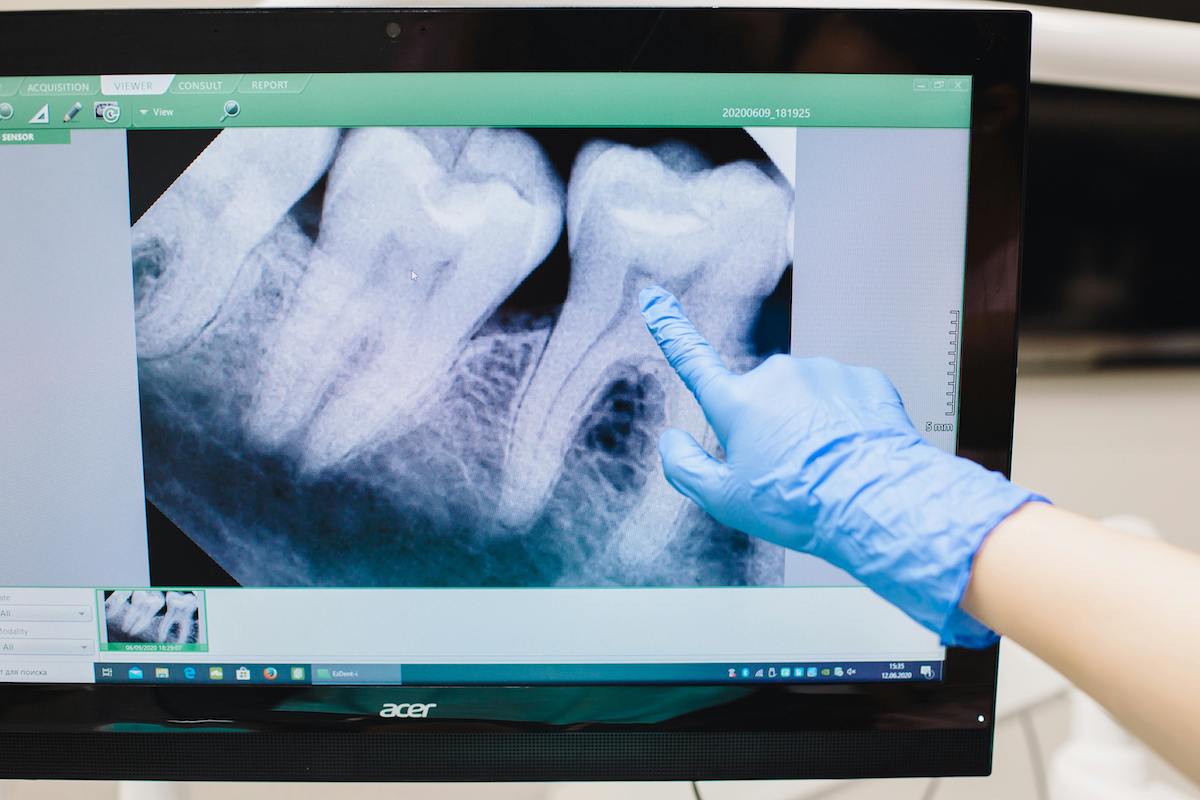

Realizamos extracciones de casos especialmente complejos como los terceros molares (más conocidos como “muelas del juicio”); tratamientos de problemas relacionados con la articulación temporomandibular (ATM); biopsias y fenestraciones de paladar para facilitar la erupción o el movimiento de los caninos impactados.